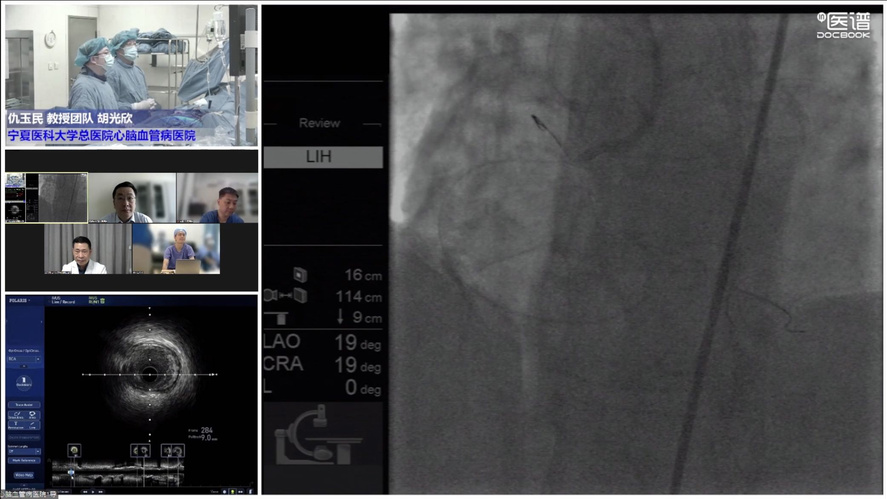

COE卓越中心成立旨在实现头部、地市、县域各医疗中心的联动,实现远程会诊与指导交流。疫情虽然隔绝各地区线下交流,但技术持续发展,远程需求快速增长,必将成为未来发展大趋势。其次希望通过COE中心将多年发展的影像数据进行收集整理发掘更多价值。第三是标准化培训体系建立,既可开展线上远程教学又可在疫情缓解时线下手把手教学,实现上下实时互动。波士顿科学始终对国内影像学与功能学技术的发展充满信心,也希望在波科本土化的进程中,与中国专家共同促进技术创新,服务广大中国患者。会议期间,四川大学华西医院、西安交通大学第一附属医院、南方医科大学南方医院、新疆医科大学第一附属医院、宁夏医科大学总医院心脑血管病医院联袂呈现17例高质量手术直播,所有与会专家各抒己见,畅谈影像技术实战应用。其中四川大学华西医院何森教授带来IVUS指导下LAD重度狭窄伴钙化手术一例。陈勇教授演示一例IVUS指导下的多支血管病变手术;周名纲教授演示一例一月内二次处理的多支病变复杂手术。王勉教授演示一例IVUS指导下逆向开通LAD慢性次全闭塞手术;黄宝涛教授带来了一例IVUS指导下旋磨处理LAD严重钙化病变;李晨教授演示了一例IVSU指导下开通无残端CTO病变的病例。西安交通大学第一附属医院郭宁、张勇教授团队带来造影剂过敏患者PCI治疗,通过IVUS不仅明确病变部位的斑块性质及血管解剖情况,同时确定支架落脚点位置及支架选择。最后在IVUS指导下顺利植入三枚支架,充分展示IVUS对指导低造影剂PCI的临床价值。由南方医科大学南方医院修建成、韩渊、梁鸿彬教授团队带来IVUS指导前降支CTO无残端的病例则先后在对角支、间隔支行IVUS找到前降支开口残端,同时IVUS显示,前降支开口后走行与间隔支夹角较小,近乎平行走行。明确解剖特点后果断决定逆向策略,最终在IVUS指导下,逆向导丝成功进入前降至病变部位远端建立导丝轨道,手术迎来完美结果。宁夏医科大学总医院心脑血管病医院仇玉民、胡光欣教授带来一例右冠CTO病例,残端似乎存在微通道,本计划行ADR,首次尝试正向开通时选择波士顿科学Sentai导丝家族Fighter导丝,仇教授提到该款导丝操控性极佳,头端硬度1.5g,外径0.09"直接通过微通道越过病变部位到达右冠远端,成功建立轨道。正确选择导丝取得开门红后,在IVUS指导下顺利植入一枚支架,迅速完成了这例颇具挑战的手术。精彩的手术演示不仅深度传递腔内影像学与功能学指导下优化PCI治疗的理念,更详细阐述IVUS的规范操作和读图技巧,在理论与实践两方面,实现知行合一。